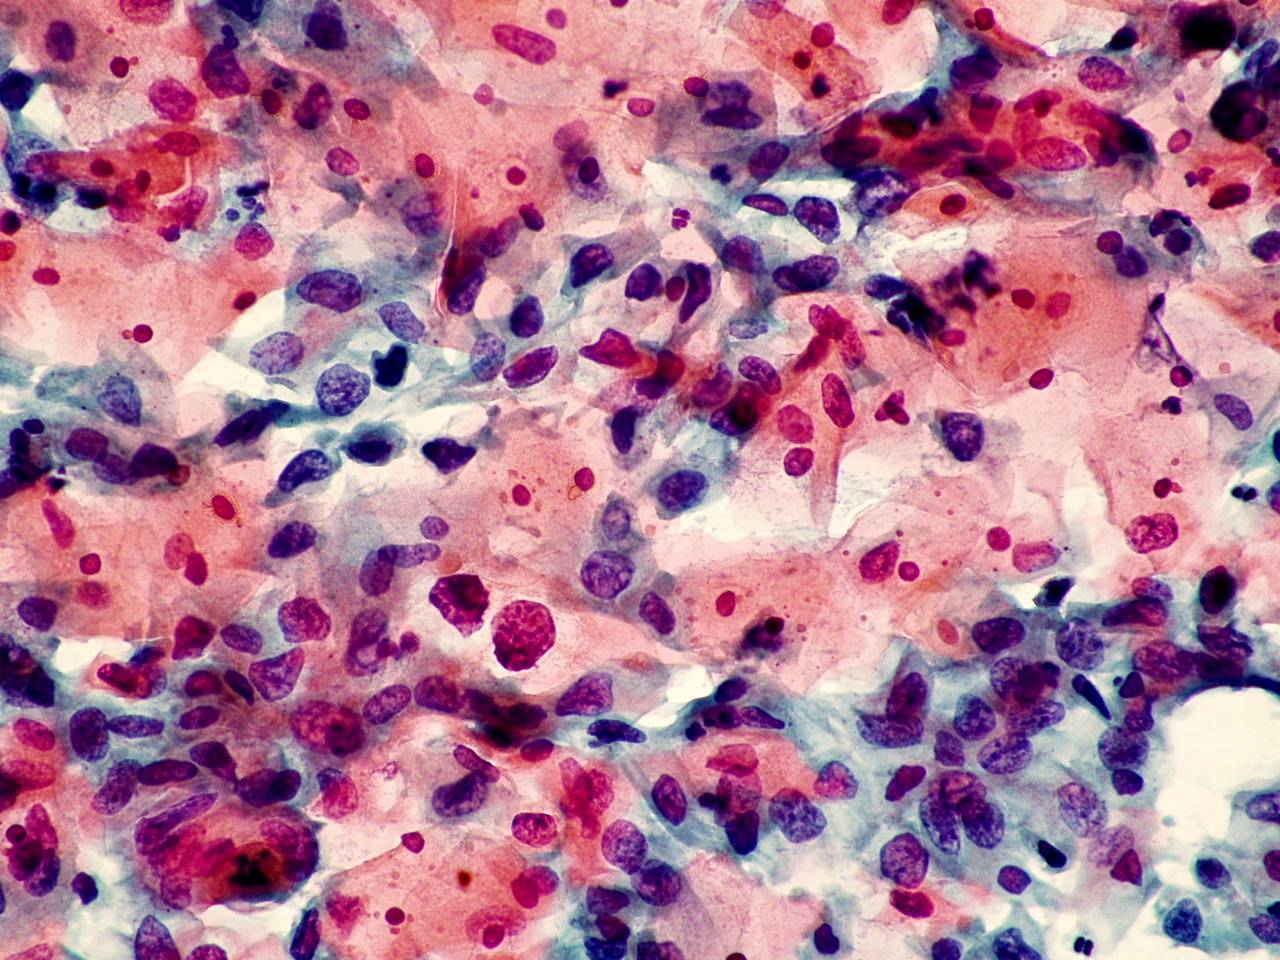

TBS-62.鳞癌

TBS-63.鳞癌

TBS-64.鳞癌

TBS-65.鳞癌

TBS-66.鳞癌